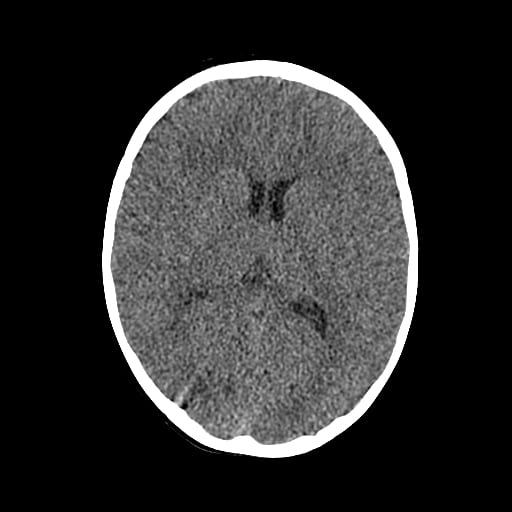

Age: 1

Sex: Male

Indication: Fall